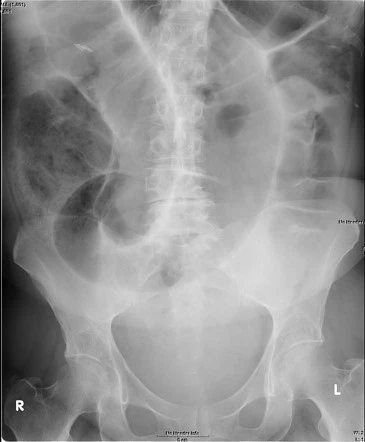

Tu obtiens rapidement un ASP de débrouillage :